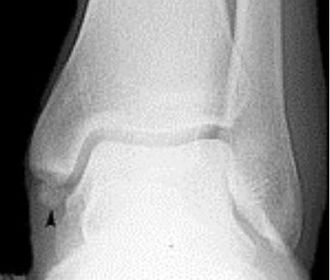

| What is this? | Os subtibiale |